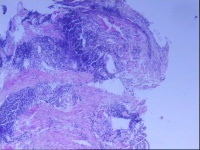

贲门黏膜,请教老师们

性别

男

年龄

59岁

临床诊断

一般病史

胃疼6年

标本名称

贲门黏膜

大体所见

灰白色小组织5块,直径约0.1-0.2CM。

图2